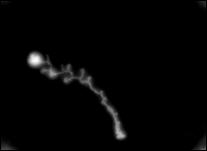

Herpesinfektion der Hornhaut. Diese Erkrankung macht sich zunächst nur als Fremdkörpergefühl, später mit Rötung bemerkbar. Solche lästigen Empfindungen gibt es auch bei trockenen Augen. In Gegensatz dazu droht hier Sehschärfenverlust oder sogar Verlust des Auges. Frühzeitig behandelt sind Komplikationen vermeidbar. Verschleppt sieht's so aus wie auf dem nebenstehenden Bild!

fortgeschrittene Herpesinfektion